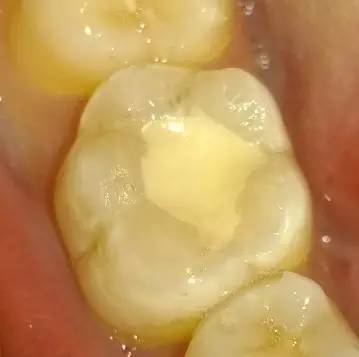

和牙色相近的填充物能预防裂缝和龋齿么?

而和牙色相近的填充材料(例如树脂和玻璃离子充填物)与牙齿之间粘合起来后,咀嚼力能均匀分布在整个牙齿上。

与银汞填充物相比,这种材料能使牙齿的坚固程度提升15%至20%,咬合力分布得更均匀意味着牙齿出现裂缝的可能性大大降低。

和牙色相近填充物的优势

但这种材料的优势在于牙医很容易发现出问题的牙齿。这是因为一旦充填物边缘变色很容易被发现。